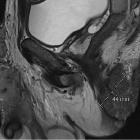

extraordinary case of Buschke–Lowenstein tumor: multiple localization, malignant transformation, and clinical insights—a case presentation and literature review. MRI image of the inguinal and penile lesions

An

extraordinary case of Buschke–Lowenstein tumor: multiple localization, malignant transformation, and clinical insights—a case presentation and literature review. MRI image of the perineal and inguinal lesions

An

extraordinary case of Buschke–Lowenstein tumor: multiple localization, malignant transformation, and clinical insights—a case presentation and literature review. MRI image of the perineal lesion